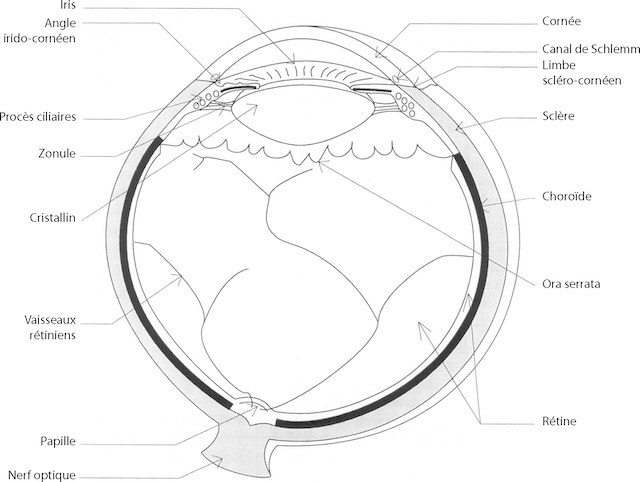

On définit classiquement un contenant formé de trois « enveloppes » ou « membranes » et un contenu (fig. 1.1).

Ce schéma représente une coupe anatomique très détaillée de l’œil humain, dessinée avec précision pour montrer l’agencement finement coordonné des structures visuelles. On y distingue la cornée à l’avant, qui laisse passer la lumière, suivie par la chambre antérieure bordée de l’iris et de l’angle irido-cornéen, où se situe le canal de Schlemm, petit mais essentiel pour le drainage du liquide intraoculaire. Juste derrière, le cristallin suspendu par les fibres de la zonule aux procès ciliaires ajuste sa courbure pour permettre la mise au point. La lumière continue son trajet jusqu’à la rétine, en passant par un milieu transparent et parfaitement organisé. On y observe la choroïde, riche en vaisseaux, qui nourrit la rétine, ainsi que la sclère qui forme la coque protectrice de l’œil. L’ora serrata marque la fin de la partie photosensible de la rétine. Enfin, la papille optique et le nerf optique signalent le point de départ du message visuel vers le cerveau. Ce type d’image, simple mais rigoureusement conçue, permet de comprendre d’un seul regard le fonctionnement de notre vision.

1 Contenant

a Membrane externe ou coque cornéosclérale

La membrane externe est constituée en arrière par une coque fibreuse de soutien, la sclère, prolongée en avant par la cornée transparente; sur la sclère viennent s’insérer les muscles oculomoteurs; la jonction entre sclère et cornée est dénommée limbe sclérocornéen. La partie antérieure de la sclère est recouverte jusqu’au limbe par la conjonctive. La sclère présente à sa partie postérieure un orifice dans lequel s’insère l’origine du nerf optique, dénommée tête du nerf optique ou papille.

b Membrane intermédiaire ou uvée

La membrane intermédiaire est constituée d’arrière en avant par :

- • la choroïde, tissu essentiellement vasculaire responsable de la nutrition de l’épithélium pig-mentaire et des couches externes de la rétine neurosensorielle;

- • les corps ciliaires dont la portion antérieure est constituée par les procès ciliaires responsables de la sécrétion d’humeur aqueuse et sur lesquels est insérée la zonule, ligament 5suspenseur du cristallin, et par le muscle ciliaire, dont la contraction permet l’accommodation par les changements de forme du cristallin transmis par la zonule;

- • l’iris, diaphragme circulaire perforé en son centre par la pupille, dont l’orifice est de petit diamètre à la lumière vive (myosis) et de grand diamètre à l’obscurité (mydriase). Le jeu pupillaire est sous la dépendance de deux muscles : le sphincter de la pupille et le dilatateur de l’iris.

c Membrane interne ou rétine (fig. 1.2)

La membrane interne s’étend à partir du nerf optique en arrière et tapisse toute la face interne de la choroïde pour se terminer en avant en formant une ligne festonnée, l’ora serrata; la rétine est constituée de deux tissus : la rétine neurosensorielle et l’épithélium pigmentaire :

- • la rétine neurosensorielle est composée des premiers neurones de la voie optique comprenant les photorécepteurs (cônes et bâtonnets), les cellules bipolaires et les cellules ganglionnaires dont les axones constituent les fibres optiques qui se réunissent au niveau de la papille pour former le nerf optique. Avec le nerf optique cheminent les vaisseaux centraux de la rétine (artère centrale de la rétine et veine centrale de la rétine) qui se divisent en plusieurs pédicules juste après leur émergence au niveau de la papille; les vaisseaux rétiniens sont responsables de la nutrition des couches internes de la rétine;

- • l‘épithélium pigmentaire constitue une couche cellulaire monostratifiée apposée contre la face externe de la rétine neurosensorielle.

2 6Contenu

Le contenu est constitué de milieux transparents permettant le passage des rayons lumineux jusqu’à la rétine.

a Humeur aqueuse

Liquide transparent et fluide, l’humeur aqueuse remplit la chambre antérieure, délimitée par la cornée en avant et l’iris en arrière. Sécrétée en permanence par les procès ciliaires, l’humeur aqueuse est évacuée au niveau de l’angle iridocornéen à travers le trabéculum dans le canal de Schlemm qui rejoint la circulation générale; une gêne à son évacuation provoque une élévation de la pression intraoculaire (valeur normale : inférieure ou égale à 21 mmHg).

b Cristallin

C’est une lentille biconvexe, convergente, amarrée aux procès ciliaires par son ligament sus-penseur, la zonule. Elle est capable de se déformer par tension ou relâchement de la zonule sous l’effet de la contraction du muscle ciliaire, et de modifier ainsi son pouvoir de convergence. Cela permet le passage de la vision de loin à la vision de près qui constitue l’accommodation; la perte du pouvoir d’accommodation du cristallin avec l’âge est responsable de la presbytie qui nécessite le port de verres correcteurs convergents pour la lecture.

c Corps vitré

Il s’agit d’un gel transparent, entouré d’une fine membrane, la hyaloïde, qui remplit les 4/5e de la cavité oculaire et tapisse par sa face postérieure (hyaloïde postérieure) la face interne de la rétine.